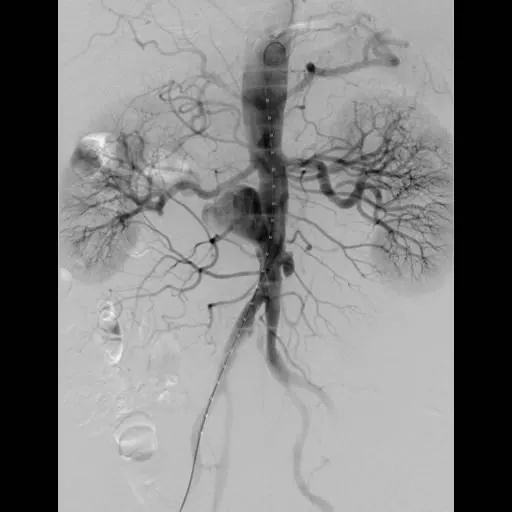

术前造影